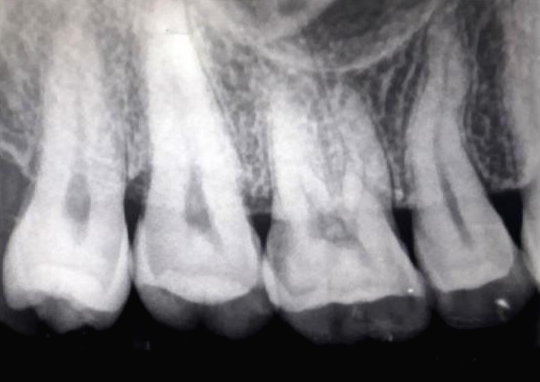

▲ 치아의 3분의 2를 덮고 있는 건강한 잇몸

▲(좌) 건강한 잇몸/ (우) 이미 많이 내려앉은 잇몸

▲ 이렇게 잇몸이 내려앉게 되면 미관상으로도 좋지 않은 것 같아요ㅠㅠ..